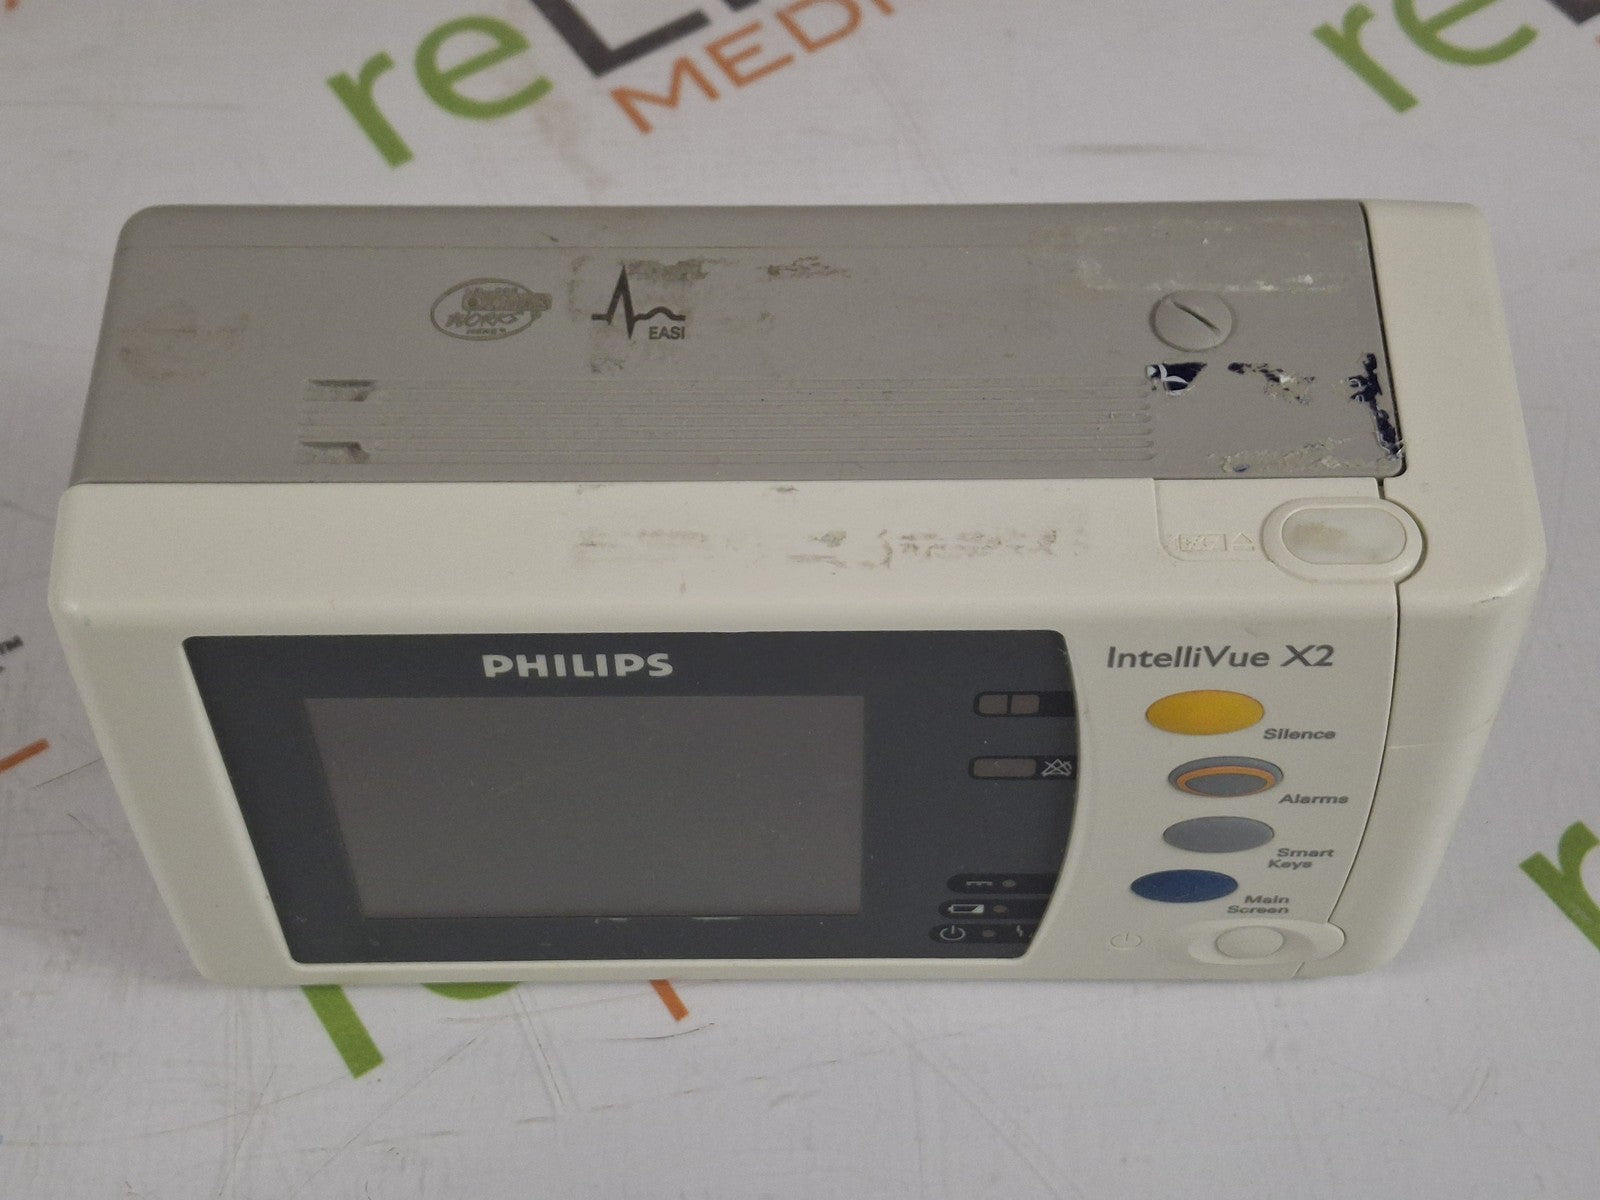

PHILIPS INTELLIVUE MX450 BEDSIDE PATIENT MONITOR

Sale price$ 1,500.00

PHILIPS INTELLIVUE MX450 BEDSIDE PATIENT MONITOR

Sale price$ 1,500.00